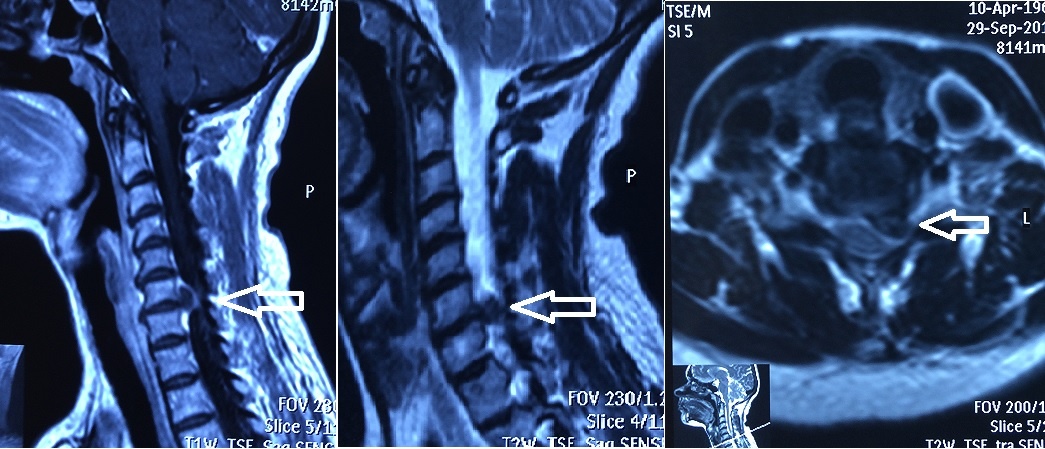

Большая грыжа со сдавлением корешка и спинного мозга